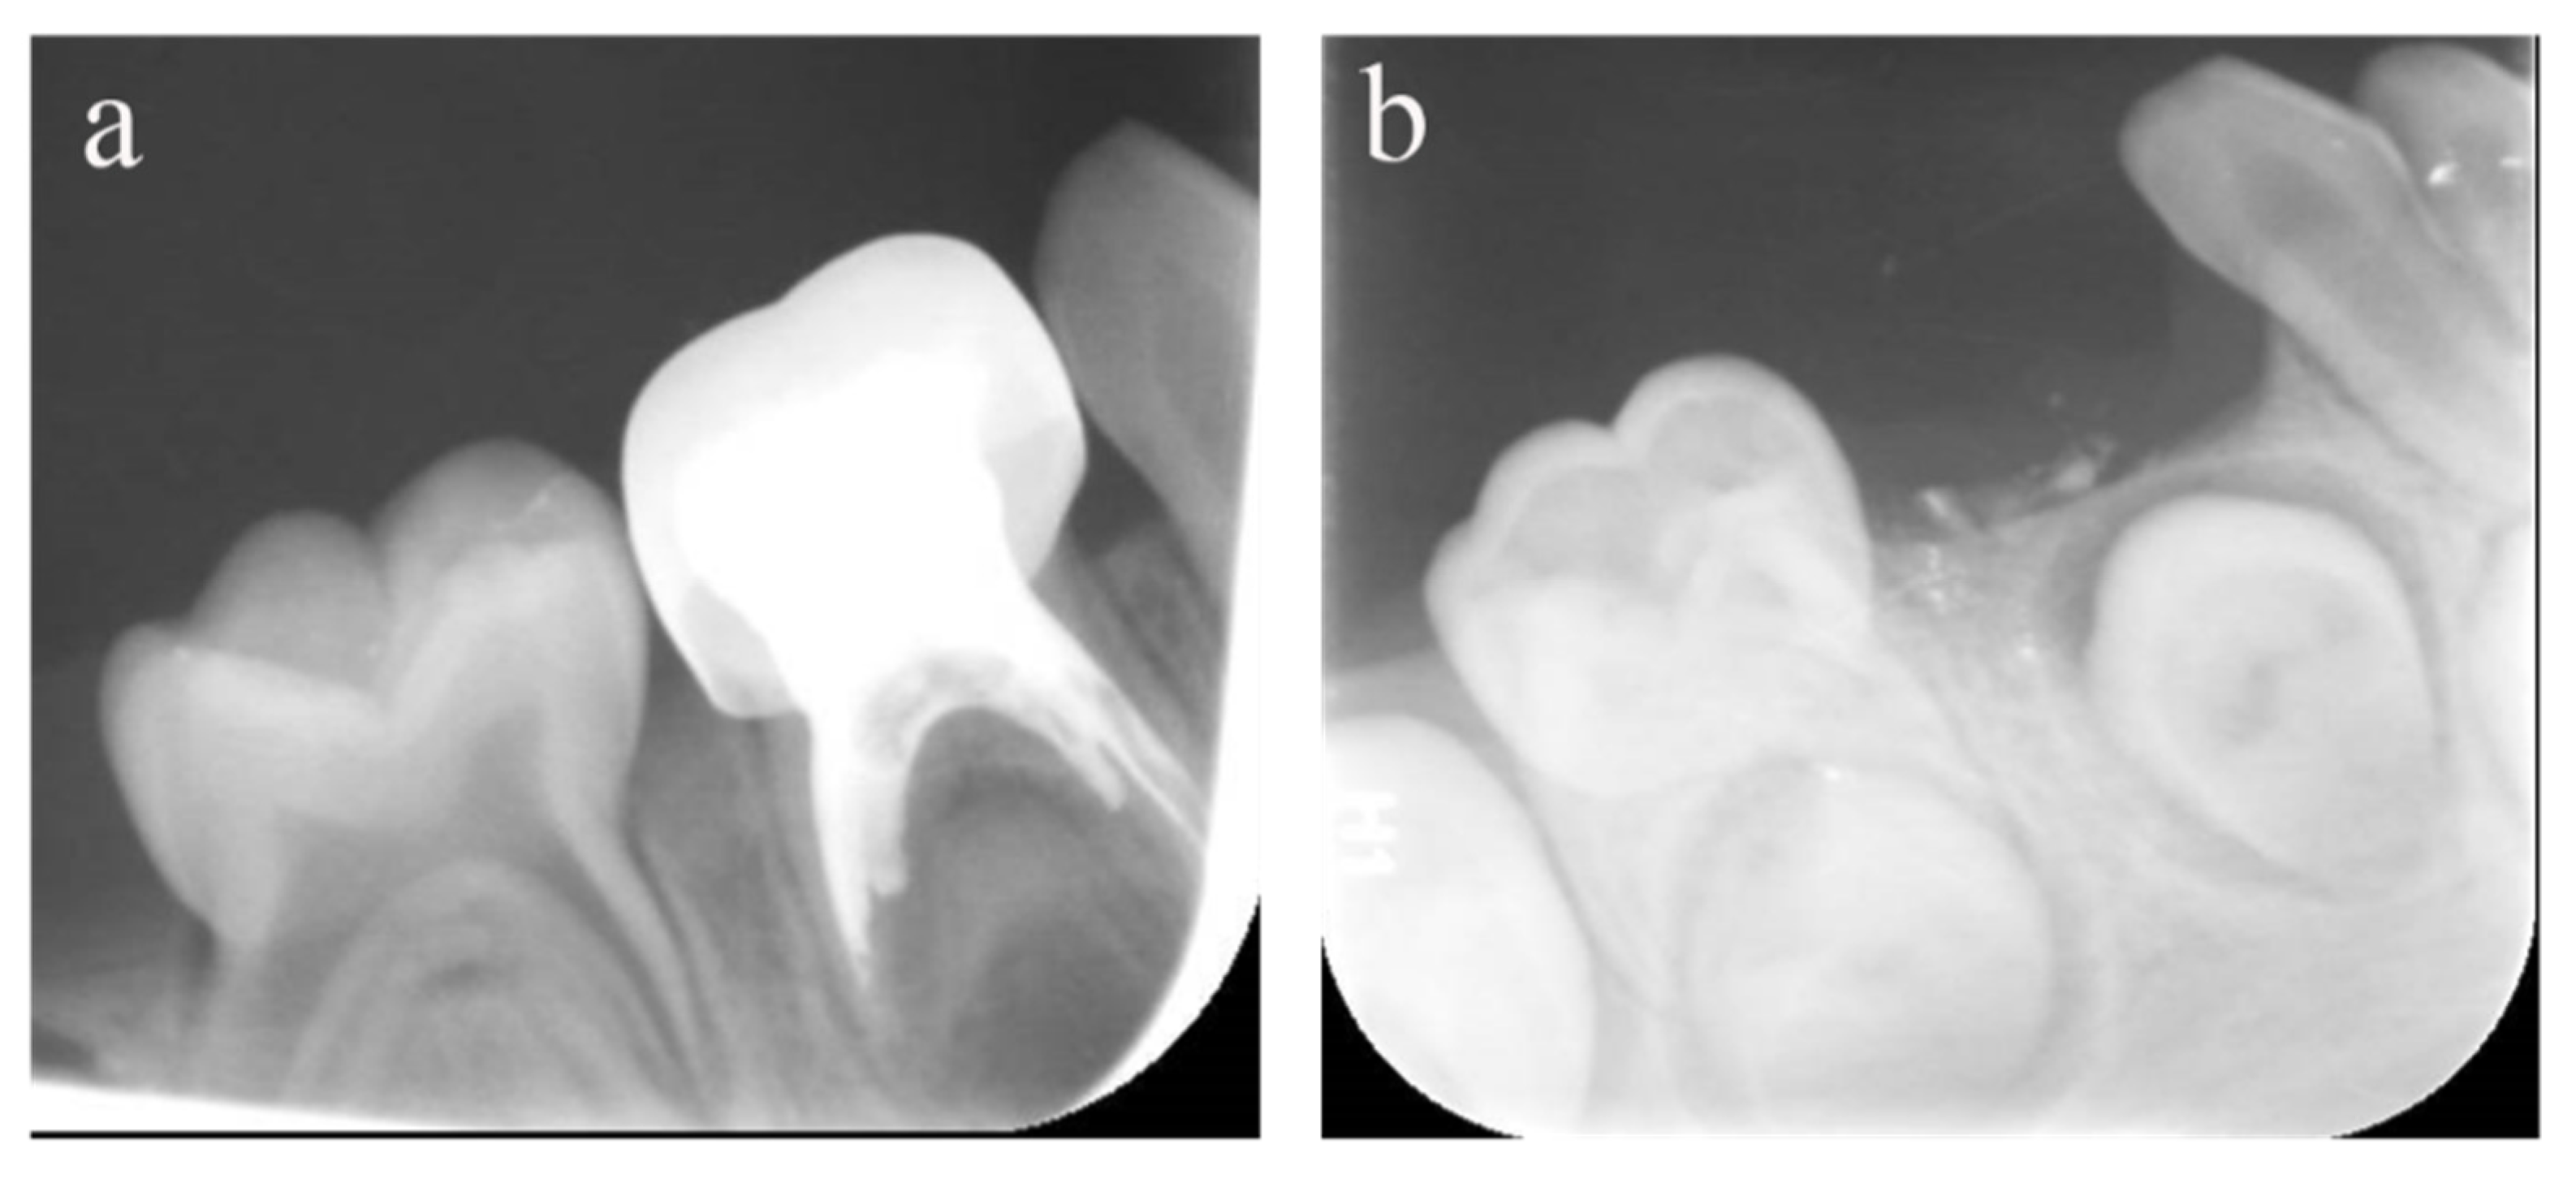

Figure 3.

#84 was treated with pulpectomy and filled with ZOE under DGA. The follow-up period was 34 months (31-month-old male child) (a) Two weeks after the operation, the radiographic showed that the filling in the distal roots was underfilled. (b) Thirty-four months after treatment, #84 was lost early, but a portion of the ZOE particles remained. The pulpectomy in #84 failed.

Figure 4.

#51, #61, and #62 received pulpectomies under DGA with a 12-month follow-up period (57-month-old female child). (a) Preoperative radiograph and #61 revealed periapical radiolucency. (b) Two weeks later, the postoperative radiograph showed underfilling in #61 and optimal filling in #51 and #62. (c) Radiograph taken 12 months postoperatively showing nothing abnormal about #62 and a periapical radiolucency surrounding the root apical of #51. Moreover, a radicular cyst occurred surrounding the apical root of #61, and the eruption direction of #21 was altered. Pulpectomies in #62 succeeded but failed in #51 and #61.